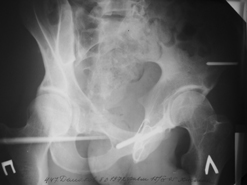

Диагноз : Сочетанная травма. ЗЧМТ. Перелом свода черепа. Ушиб головного мозга.Разрыв лонного и крестцово-подвздошного сочленений с нарушением целостности тазового кольца, с массивной забрюшинной гематомой и пропотеванием в брюшную полость. Перелом 10 ребра справа, осложненный гемопневмотораксом справа, правосторонней пневмонией на фоне ушиба правого легкого. Шок 3-4 ст. Больной поступил в отделение 07.03.2005г. в 16.00 в экстренном порядке через 30 минут после автодорожной травмы.Доставлен КСП. При поступлении состояние больного крайне тяжелое, явления травматического шока, А/Д-80/60 мм.рт. ст. ЧСС-120.В экстренном порядке поднят в операционную, интубирован, совместно с диагностическими мероприятиями лечение шока.При осмотре выявлены перелом 10 ребра справа, разрыв лонного и правого крестцово-подвздошного сочленений. Имеется линейный перелом теменной и височной костей слева с переходом на основание. Диагностическая лапароскопия 07.03.2005г. в 16.30-массивная забрюшинная гематома малого таза.Оставлена контрольная, дренажная трубка.Учитывая кровь в моче произведена цистография - данных за разрыв мочевого пузыря не найдено. Больной переведен в реанимационное отделение.За 08.03.2005г. из брюшной полости выделилось до 1500,0 мл, крови, часть крови реинфузирована. 08.03. в 06.30 наложен торокоцентез справа,удалено 100,0 мл. крови и 200,0 мл. воздуха .. Учитывая продолжающеееся кровотечение в брюшную полость из перелома костей таза, для исключения возможного разрыва внутренних органов 09.03.2005г. произведена Видеолапароскопия., на которой повреждения органов брюшной полости не выявлено.Одновременно произведен шов лонного сочленения проволокой и винтами, с одномоментным наложением стержневого аппарата на кости таза, с целью уменьшения кровотечения из разрывов тазовых сочленений, дренирование гематом. В последующем состояние больного оставалось тяжелым. 10.03.наложена нижняя трахеостома.Далее неоднократно производилась лечебно-диагностическая ФБС.С 10.03 выявлена правосторонняя плевропневмония. КТ головного мозга от 10.03-субарахноидальноекровоизлияние.Срединные структуры не смещены. КТ-контроль от 15.03-открытая моновентрикулярная гидроцефалия4 желудочка. Полисинусит. Постепенно состояние больного медленно прогрессировало к улучшению.С 24.03 переведен на самостоятельное дыхание, а 09.03 переведен в травматологическое отделение.Аппарат стержневой снят из-за перелома стержня (раскрутил больной самостоятельно).После госпитализации в наше отделение проведено дополнительное обследование Рентгекнография, КТ.Хотелось бы услышать Ваше мнение о дальнейшей тактике.-- С уважением, Leonid

Углядел билатеральное повреждение таза. Имеется вертикальная нестабильность со стороны перелома боковой массы крестца, ротационная с контрлатеральной стороны - чрезподвздошный разрыв кп сочленения. Разрыв лона, запирательные отверстия вроде целы.

DS. на сегодняшний день: Вертикальная двусторонняя нестабильная деформация таза, неправильно срастающийся перелом боковой массы крестца слева, срастающийся перелом крыла правой подвздошной кости, застарелый частичный разрыв правого кп сочленения, застарелый разрыв лонного сочленения.